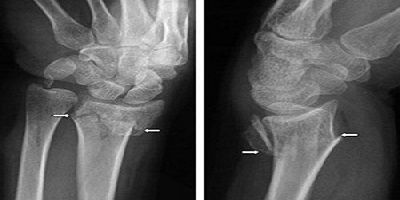

Ortopedi Ve Travmatoloji

ORTOPEDİK REHABİLİTASYON

Ortopedik Rehabilitasyon Ortopedik rehabilitasyon, konservatif yada cerrahi tedavi gerektiren kas-iskelet sistemine ait tüm ortoped...